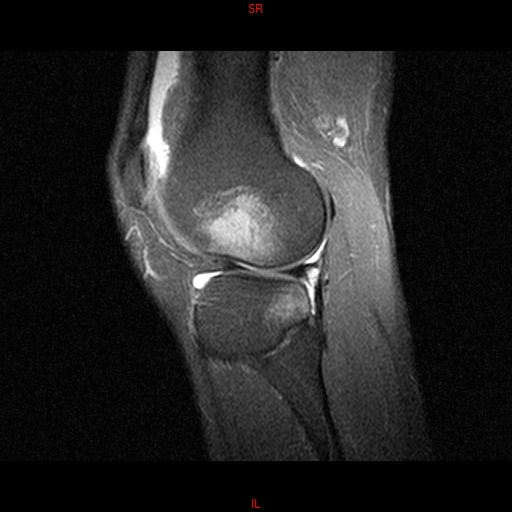

• RESONANCIA PATOLÓGICA MENISCOPATIA INTERNA DP SAGITAL

• RESONANCIA NORMAL RODILLA SAG DENSIDAD PROTONICA